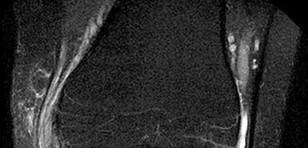

Question 19

A 42-year-old weekend warrior sustains a sudden "pop" in his posterior calf while lunging for a tennis ball.

He is diagnosed with an acute Achilles tendon rupture via a positive Thompson test. He opts for non-operative management utilizing an early functional rehabilitation protocol. Based on modern Level I evidence, how does this approach compare to operative repair?

Explanation

Historically, traditional cast immobilization for Achilles ruptures had higher rerupture rates than surgery. However, modern Level I randomized trials (e.g., Willits et al.) have demonstrated that non-operative management coupled with an early functional rehabilitation protocol (early weight-bearing in a functional orthosis and early ROM) yields rerupture rates that are statistically equivalent to operative repair. The primary advantage of the non-operative functional approach is the complete avoidance of surgical complications, such as wound breakdown, deep infection, and iatrogenic sural nerve injury.